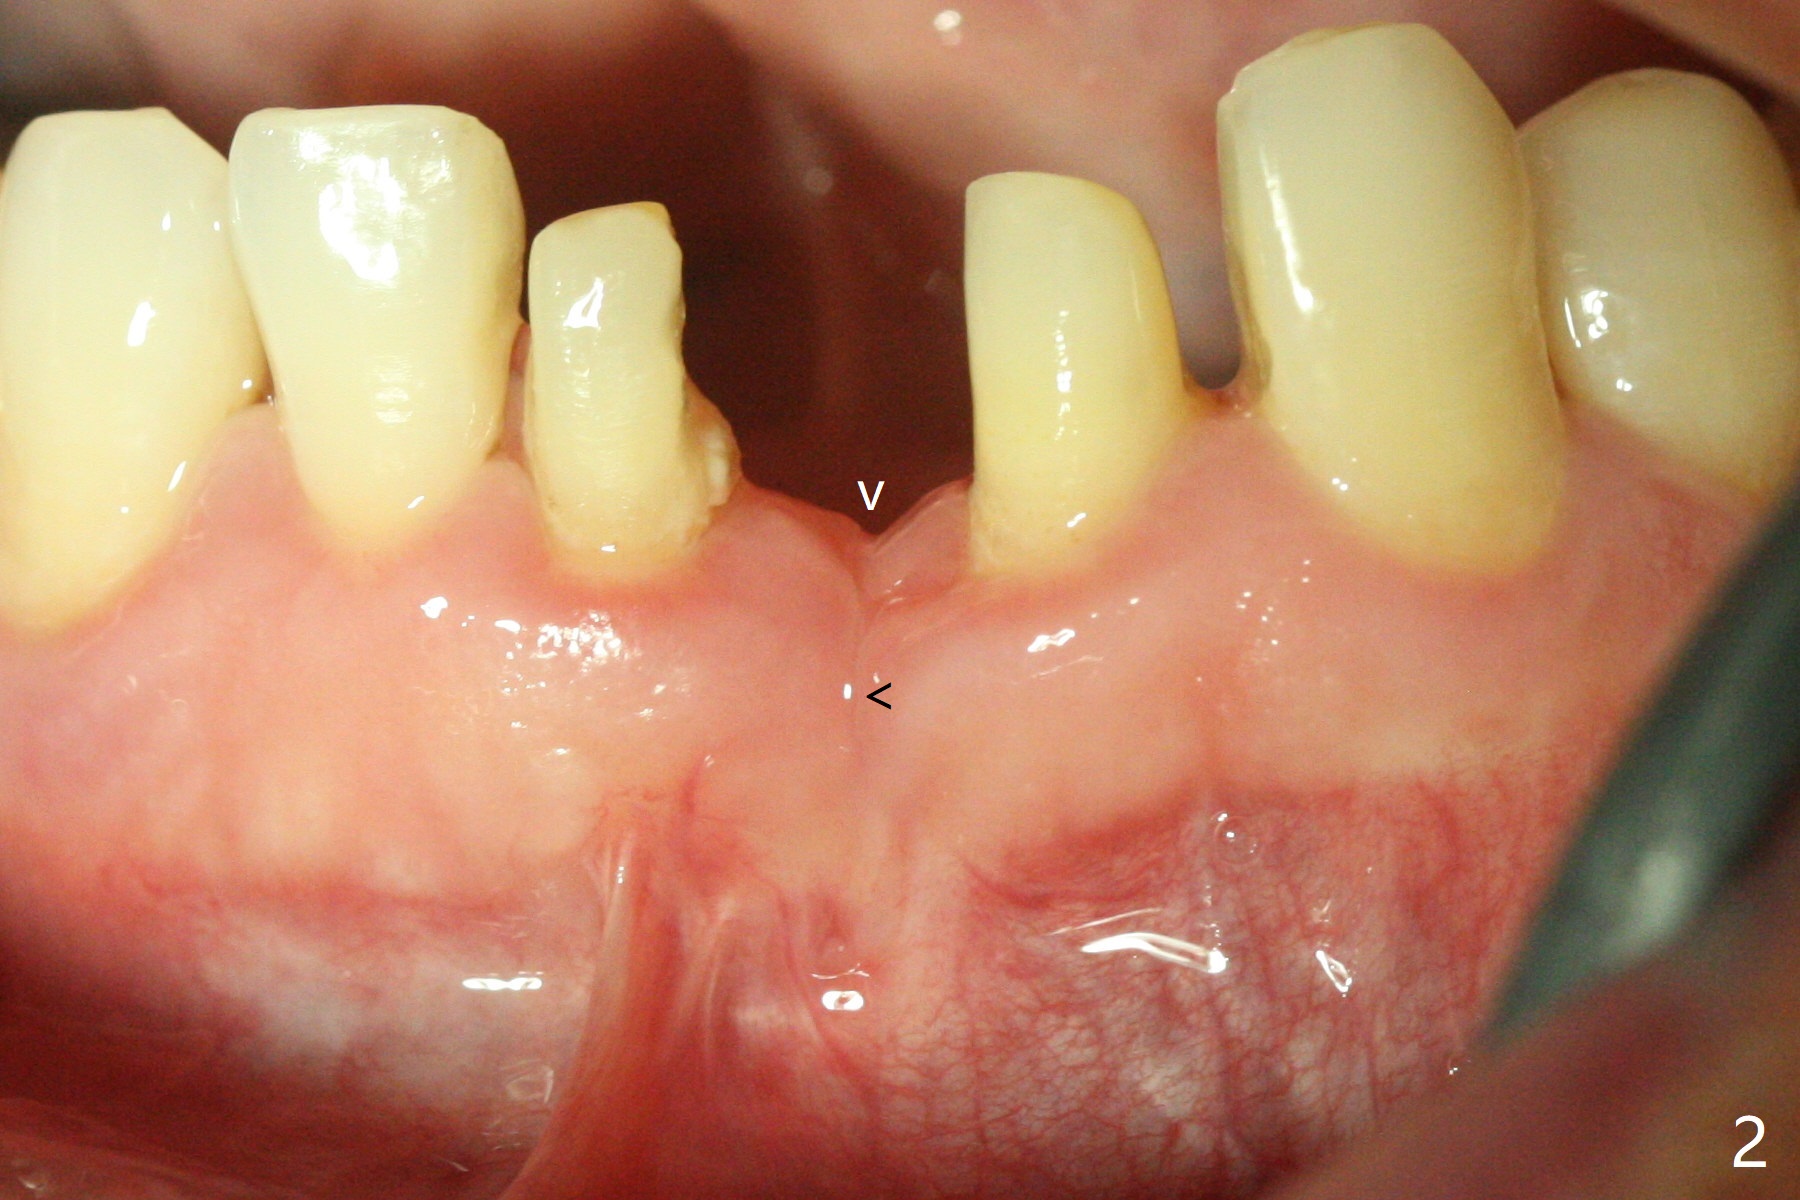

经过深洗以及改善口腔卫生,术前下前牙区牙龈基本没有红肿,但是缺牙处牙龈凹陷(图一,二:箭头),这个现象代表什么?如何影响手术进路?其实后者部分是因为牙龈与下面骨质(骨嵴)粘连(图三:*)产生的,分离粘骨膜瓣时不小心撕裂颊侧牙龈(图三(骨膜分离器下面:#),造成后来缝合困难,需要多用一个胎盘膜)。如果术前仔细分析CT 3D图像(图四,五)可以发现严重颊侧骨壁凹陷(图三:^)以及骨嵴(图四:*),事先抽血制备PRF膜和粘性骨粉,植骨效果好些(图六)。术中发现缺损,再抽血会拖延手术。最后将就用血调袢骨粉,使用胶原膜和胎盘膜覆盖(图七,八)。颊侧裂口术后十天愈合了(图九,十)。术后一个月颊侧牙龈凹陷,牙桥边缘(图十一:箭头)粗糙,临时牙桥取出,调整边缘,有利于局部卫生(图十二)。术后两个月桥边缘光滑(图十三:箭头),局部卫生和牙龈凹陷有所改善。病人将一个半月后回来取模。Return to Protect Graft 前磨牙即种 101 Xin Wei, DDS, PhD, MS 1st edition 04/30/2021, last revision 07/03/2021